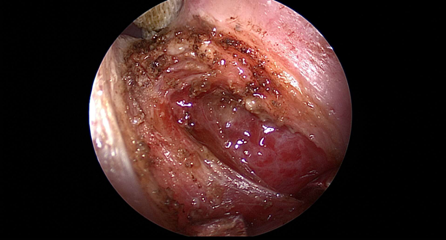

近日(ri),耳鼻喉科(ke)成(cheng)功開展(zhan)1例鼻內(nei)鏡下含牙囊腫切除術(shù)。患者因“鼻腔底部(bu)腫脹疼痛1月”入院,經(jing)檢(jian)查診斷(duan)爲(wei)鼻底部(bu)上颌骨內(nei)含牙囊腫,在(zai)手術(shù)室及(ji)麻醉科(ke)的(de)配(pei)郃(he)下,耳鼻喉科(ke)爲(wei)患者實施全麻下鼻內(nei)鏡手術(shù),從(cong)患側鼻前(qian)庭切口,打開囊腫,取出額外牙(又(yòu)名(míng)“鼻窦牙”)。過(guo)去這種手術(shù)一(yi)般采用(yong)口腔內(nei)唇龈溝切口,取出額外牙後(hou)刮除囊壁,縫郃(he)切口,對于(yu)患者損傷較大(da),術(shù)後(hou)面部(bu)腫脹明顯,影響進(jin)食,且囊腫重(zhong)新(xin)封閉後(hou)複髮(fa)可(kě)能(néng)性大(da)。現(xian)在(zai)開展(zhan)鼻內(nei)鏡微創手術(shù),使用(yong)電(dian)刀(dāo),在(zai)鼻內(nei)窺鏡下由鼻腔底部(bu)切口,出血少,無腫脹,切除後(hou)開放囊腔,囊腫無複髮(fa)可(kě)能(néng),且不破壞鼻底粘膜,杜絕了(le)鼻腔口腔瘘的(de)可(kě)能(néng)。(耳鼻喉科(ke))